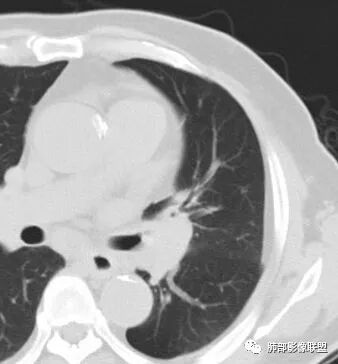

南边:临床:老年男性,病史偏长,2月。临床有通气功能障碍。

我们看影像,肺内有一些小斑点状高密度影,部分区域有气体潴留:

南边:我们现在影像上看的,也就是肺部小斑点,这些斑点,有些地方有气道储留的一个特点。

南边:但是我们看纵隔就多发的肿大淋巴结,部分融合成团。

南边:而且这些淋巴结,有些直接主要是压迫支气管壁,但是有些是突入到支气管腔内的。可惜我截的图发不上来。就左上舌段,支气管壁明显的增厚。有些明显腔内突的一个结节的,但是远的没有阻塞的特点。南边:增强以后呢,这个病灶明显强化,部分的似乎有环形强化的迹象,但不是很典型。

我们看这个主支气管的层面,主支气管明显受压,有变形的,但是软骨是没有突破的。

南边:那也就是说,这个纵隔淋巴结,它是没有影响到我们主支气管内部去的,周围有,可惜的膜部的增厚,我总心里不踏实,后面因为食道贴在一起啦。 因此这些淋巴结在主支气管层面是没有影响的。

这个区域明显就是一个支气管本身有问题。

但是有一个地方有问题的,左侧的上叶的下舌段这个区域:

左上叶舌段这个气管腔内是有东西凸进去。